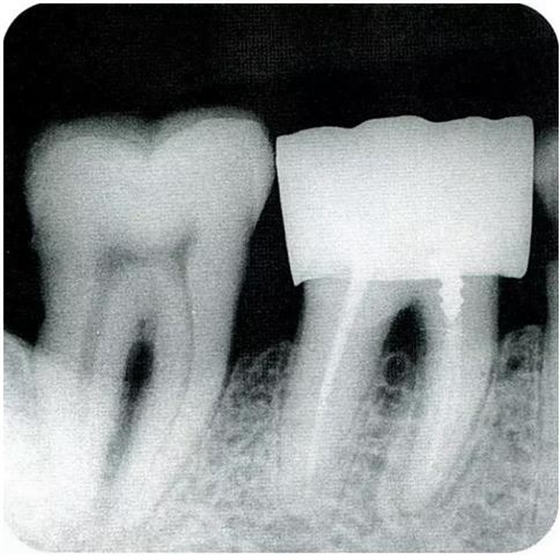

▼圖6-1下頜第一后磨牙的頰舌間存在III度的根分叉病變,預(yù)在進行牙根分割后保留遠中根。

▼圖6-2中下頜第一后磨牙雖然切除了一半,但是遠中根也有2根分根,所以不得已拔除(被拔除遠中根的近中面觀察)。